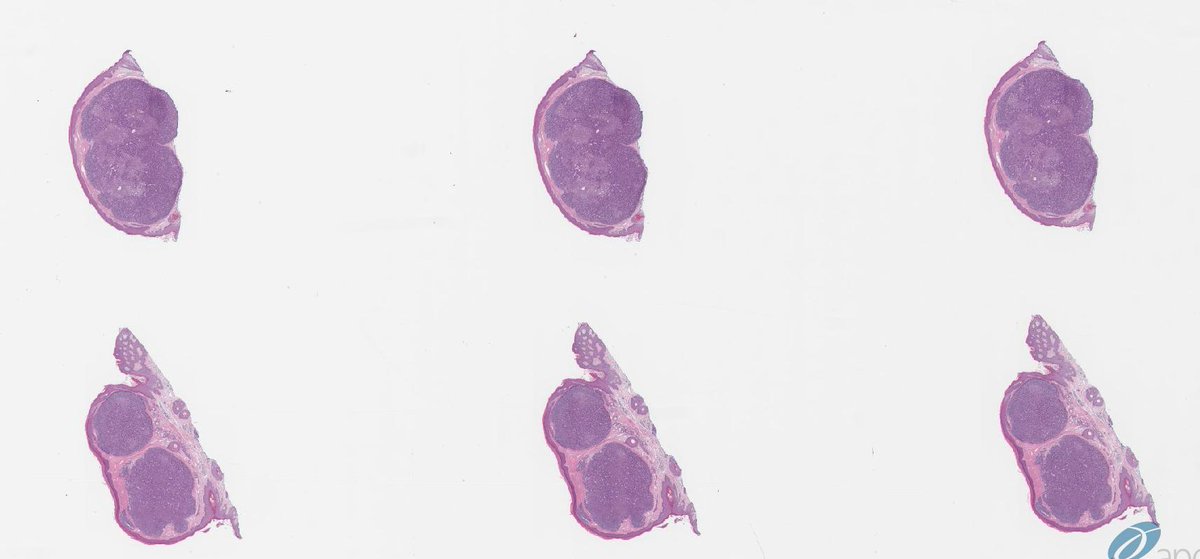

33 y/o m with single 1cm scalp erythem polypoid lesion, slowly growing #dermpath

Best diagnosis?

A. Rippled pattern sebaceoma

B. Sebaceous carcinoma

C. Rippled pattern trichoblastoma

D. Basal cell carcinoma with sebaceous differentiation

E. Sebaceous trichofolliculoma

English